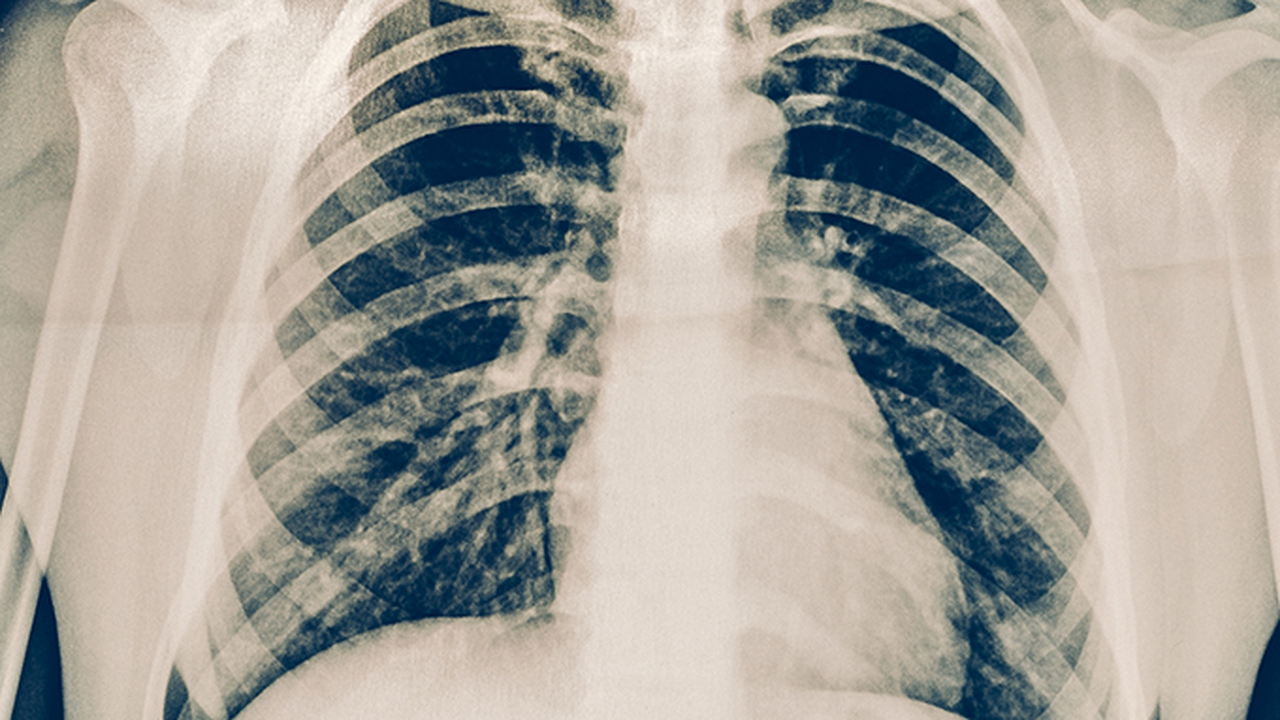

肺癌作為高發(fā)惡性腫瘤,早期診斷和規范治療對預后至關(guān)重要。廣州作為華南醫療中心,擁有多家在肺癌診療領(lǐng)域具有豐富經(jīng)驗的醫療機構,為患者提供手術(shù)、放療、化療、靶向治療及免疫治療等綜合治療方案。

肺癌預防與健康管理方面,建議40歲以上人群,特別是長(cháng)期吸煙者、有肺癌家族史者、長(cháng)期接觸致癌物質(zhì)者,應定期進(jìn)行低劑量螺旋CT篩查。日常生活中應戒煙限酒,避免接觸二手煙和廚房油煙,注意室內通風(fēng)。飲食上多攝入新鮮蔬果,適量運動(dòng),保持良好心態(tài)。出現持續性咳嗽、痰中帶血、胸痛等癥狀時(shí)應及時(shí)就醫檢查。確診肺癌后,應選擇正規醫療機構接受規范治療,并遵醫囑定期復查。